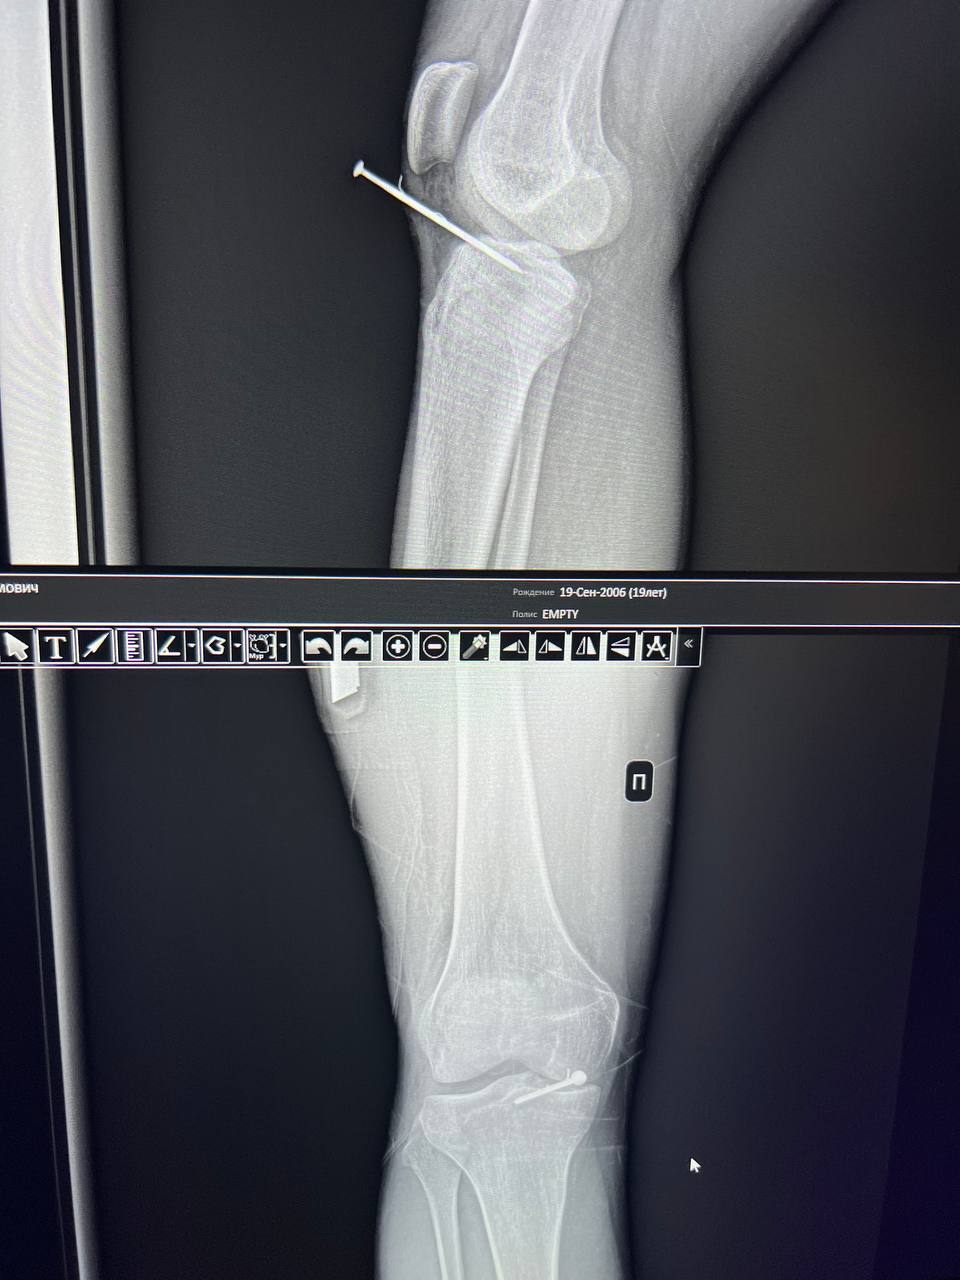

Недавно один из таких горе-строителей въехал в отделение травматологии Долгопрудненской больницы на кресле-каталке: одно неосторожное движение во время работы со строительным пистолетом – и из колена мужчины торчит длинный гвоздь. Скобяное изделие не только пробило мягкие ткани, но и накрепко застряло в кости.

Медики незамедлительно оказали помощь пострадавшему – обработали рану и извлекли гвоздь. Как и всегда при травмах с участием инородных предметов, пациенту ввели иммуноглобулиновый препарат для профилактики заражения столбняком.